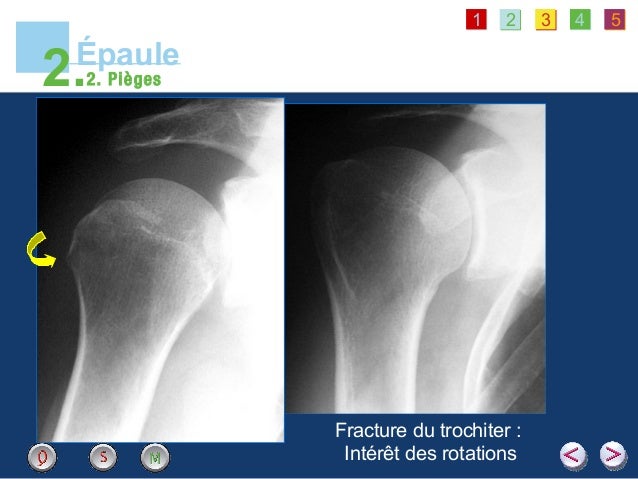

Rotation externe 45° 70° (90°) Rotation interne 30° 50° (70°) NB l’amplitude des rotations varie selon la position du bras, s’il est en abduction, elle sont plus grandes Le coude Flexion 140° 150° Extension 0° 5° Supination 90° Pronation 80°90°. Epaule douloureuse pathologie de la coiffe des rotateurs et de la = 4550° Abduction = Elevation latérale Glénohumérale = 90° Glénohumérale Scapulothoracique = 180° Rotation externe 80° Rotation Interne 90° Mouvements combinés = Main nuque (Antépulsion Rotint) Main dos (rétropulsion Rot int) Examen de l’épaule. A Rotation neutre positionnement en double obliquité, rayon descendant de à 30° et épaule controlatérale formant un angle de 45° avec la table Paume de la main contre la cuisse b Rotation interne le bras réalise une rotation interne de 45°, dos de la main contre la cuisse.

EPAULE ROTATION EXTERNE Epaule de face en rotation interne Calcifications des tendons de la coiffe Instabilités antérieures de l'épaule fracture tassement de la face postérieure de la tête humérale EPAULE ROTATION INTERNE Profil de coiffe (Lamy) Localisation d'une calcification ou d'une brèche. Similarly, passive range of external rotation increased significantly from 43 degrees / 06 degree on D0 to 135 degrees / 05 degree on D5 (P = 004) and showed a nonsignificant increase. 5e année médecine – Rotation 3 – 16/17 ISM Copy Module de Traumatologie – Orthopédie Luxations traumatiques de l’épaule Introduction / Définition La luxation de l'épaule est la perte du rapport anatomique, complet et permanent, entre 2.

Rotation neutre Tubercule majeur net et horizontal Gouttière dans le 1/4 externe de l’épiphyse Tubercule majeur Tubercule mineur Gouttière intertuberculaire Cavité glénoïdale Tête humérale Bord acromial de la clavicule Acromion Processus coracoïde Radiographies standard clichés de face Rotation latérale dégage le. Le bilan d’imagerie débute de façon systématique par des radiographies de l’épaule Elles sont prescrites par votre Médecin Traitant, votre Rhumatologue ou votre chirurgien Ce bilan se compose de Radiographie de face 3 rotations la main est orientée en rotation neutre, interne et externe permet de dévoiler les différentes “facettes” de la tête de l’humérus. Application Guide for EDrive of motorcycle has been released Nov 26, Application Guide for Smart Watch/Activity Tracker has been released Oct 16, Application Guide for Fuel Injection System in motorcycle has been released Sep 25, Application Guide for True Wireless Stereo has been released Sep 17,.